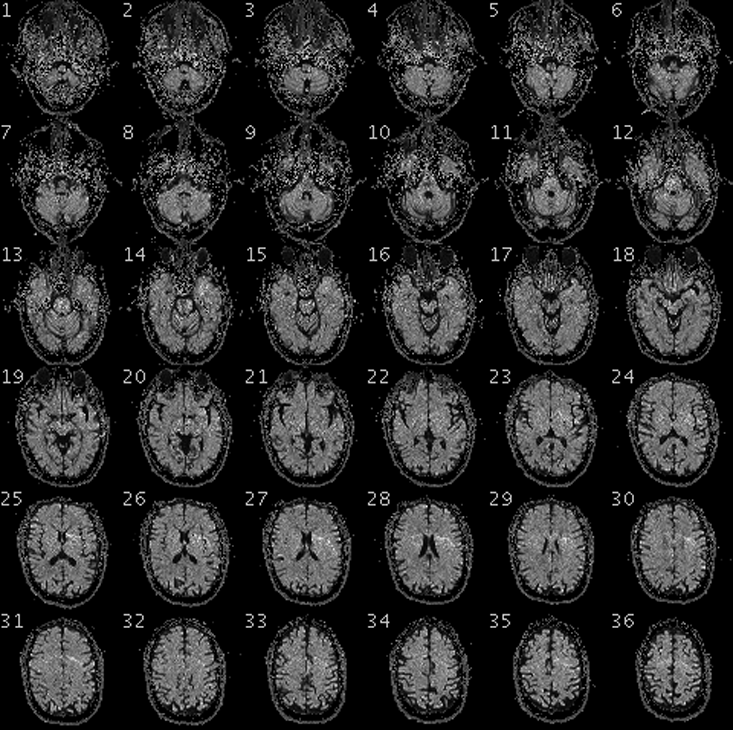

When Adrian Owen, a neuroscientist at the University of Western Ontario, asked Scott Routley to imagine playing a game of tennis, any acknowledgement would have been surprising. After all, Routely had been completely unresponsive for the 12 years since his severe traumatic brain injury. He was thought to be in a vegetative state: complete unawareness of self or environment. But, as Owen watched Routley’s brain inside a functional magnetic resonance imaging (fMRI) scanner, he saw a region of the motor cortex called the supplementary motor area—thought to play a role in movement—light up with activity. When he told Routely to relax, the activity ceased. And when he asked Routley to imagine walking around his house, he saw clear activity in the parahippocampal gyrus—a region of the brain that plays an important role in the encoding and recognition of spatial environment.

After dozens of repetitions of these mental imagery tasks, Owen was sure that Routley was conscious. Then Owen went a step further: He asked Routley to answer yes-or-no questions by directing his imagination. Imagining playing tennis stood for “yes,” and walking around his house for “no.” Routely was able to correctly identify himself (“Is your name Scott”—“yes”; “Is your name Mike”—“no”), his location (“Are you in a hospital?”—“yes”; “Are you in a supermarket?”—“no”), the current year (“Is it 1999?—“no”; “Is it 2012?”—“yes”), and the name of his personal care worker, whom he had only met after his accident. He also answered that he was not in pain, and that he enjoyed watching hockey on TV. Routley, it turned out, was not in a vegetative state. In fact, he and patients like him required a new classification, which later researchers would call cognitive motor dissociation (CMD).

Another patient, Jeff Tremblay, was incorrectly diagnosed as being in a vegetative state for over a decade before researchers realized, again using fMRI, that he was conscious. Instead of asking him to imagine performing certain tasks, neuroscientist Lorina Naci showed him a short Alfred Hitchcock film. We might not realize it while lying on the couch or sitting in a theater, but following the twists and turns of a film’s plot is a cognitively demanding experience. It requires us to integrate visual and auditory information with our existing knowledge of the world. We need to focus our attention and ignore distractors. We need to interpret behavior and language to know what the characters are thinking.

It also turns out that different people will exhibit similar brain activity in response to engaging stimuli like movies, suggesting a similar conscious experience. Owen and Naci had previously detected a characteristic pattern of brain activity in healthy participants that was closely synchronized to the plot of the Hitchcock film.2 When Naci and her team showed Tremblay the film inside an fMRI scanner, they saw this same pattern of complex mental response.